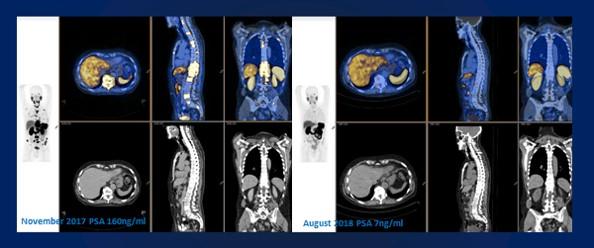

image: Marked reduction in metabolically active disease in response to a combination of 177Lu PSMA 617 + NOX66 therapy in end-stage, high-volume castrate resistant metastatic prostate cancer. The PSA continued to fall for 6 months after completion of therapy, and the patient remains well 20 months after trial enrollment.

Image: